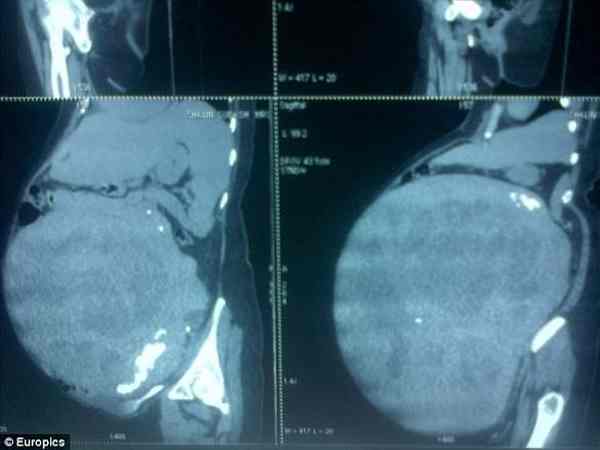

नई दिल्ली। ग्वाटेमाला की रहने वाली एक महिला के पेट में पिछले सात साल से 32 किलो का ट्यूमर था जिसे हाल ही में डॉक्टर ने ऑपरेशन करके निकाला है। डॉक्टर इसे अब तक का दुनिया का सबसे बड़ा ट्यूमर बता रहे हैं।

डॉक्टर ने बताया कि यह ट्यूमर महिला के गर्भाशय में बड़ा हो रहा था जिसकी वजह से महिला गंभीर रुप से गर्भवती लगती थी। महिला को देखने पर ऐसा लगता था जैसे उसके पेट में कई बच्चे पल रहे हों। ट्यूमर की वजह से महिला को पेट 137 तक फूल गया था। डॉक्टर ने बताया कि इस बीमारी का नाम लियोमायोमा है। लियोमायोमा एक तरह का ट्यूमर है जो जल्दी कैंसर में नहीं बदलता है।

इस महिला की पहचान छुपा ली गई है हालांकि एक मेदिकल छात्र ने इस महिला के ट्यूमर की तस्वीर figure1 नाम की एक वेसाइट पर डाला जिसके बाद दुनिया भर के डॉक्टरों को इस बार में पता चला। बता दें कि इससे पहले एक भारतीय महिला के पेट से 30 किलो का ट्यूमर निकला था जिसे इससे पहले तक दुनिया का सबसे बड़ा ट्यूमर माना जाता था।